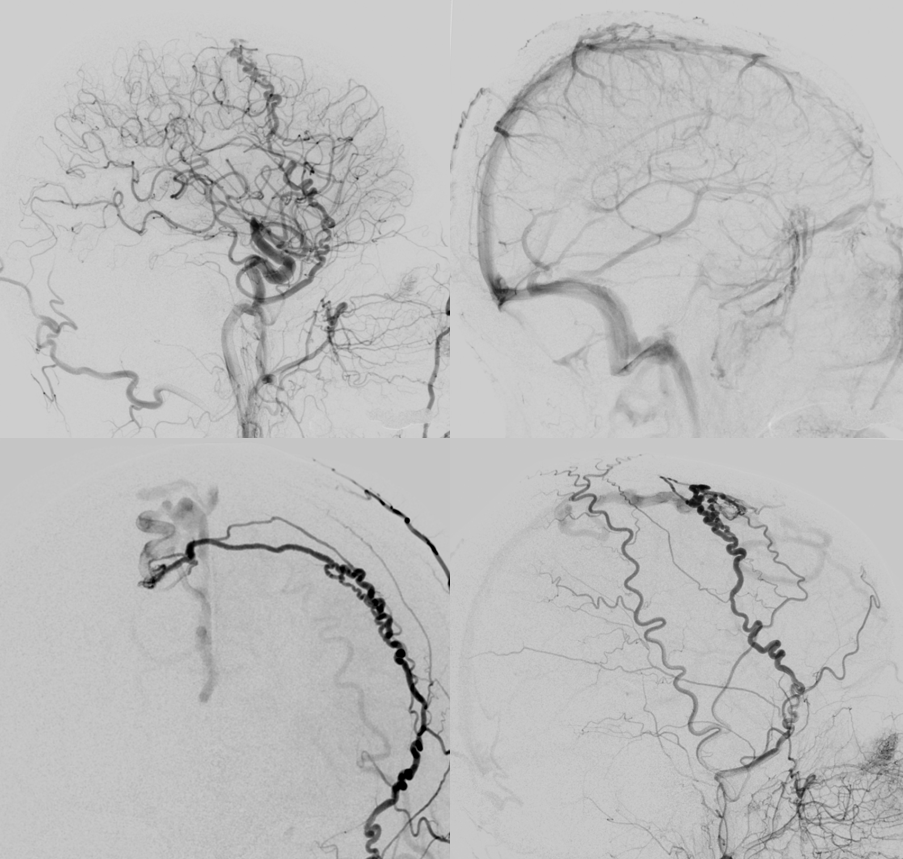

Angio — the good side

Bad side

Some venous CBCT etc